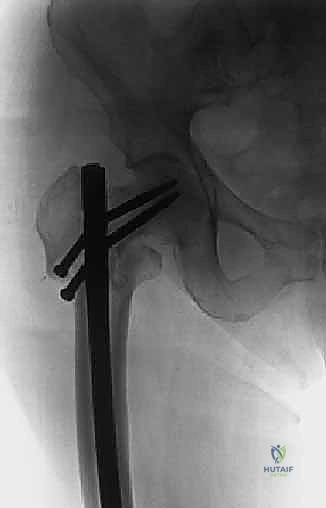

- إدارة خطر النزيف (Embolization): بعض الأورام مثل سرطان الكلى والغدة الدرقية تكون عبارة عن كتل دموية نابضة. لتجنب النزيف القاتل أثناء الجراحة، يتم إجراء "إصمام وعائي" (Angioembolization) قبل 24-48 ساعة من العملية لقطع الدم عن الورم.

- اختيار نوع المفصل الاصطناعي: بناءً على صور الأشعة المقطعية، يحدد الجراح نوع المفصل. في حالات الأورام، غالباً ما تُستخدم مفاصل ذات جذوع طويلة (Long-stem prostheses) لتجاوز منطقة الورم وتثبيت المفصل في العظم السليم أسفل الآفة. كما تُستخدم تقنية الأسمنت العظمي (Bone Cement - PMMA) بكثافة لتوفير استقرار فوري للمفصل والسماح للمريض بالمشي في اليوم التالي.

الخطوة 4: تحضير عظم الفخذ وتثبيت الجذع (Femoral Stem Insertion)

- يتم تجويف القناة النخاعية داخل عظم الفخذ لتتناسب مع حجم الجذع المعدني (Stem).

- في مرضى السرطان النقيلي، يُفضل استخدام الأسمنت العظمي لتثبيت الجذع. الأسمنت العظمي لا يعمل كصمغ فقط، بل كحشوة تملأ الفراغات التي تركها الورم وتوفر دعماً ميكانيكياً فورياً.